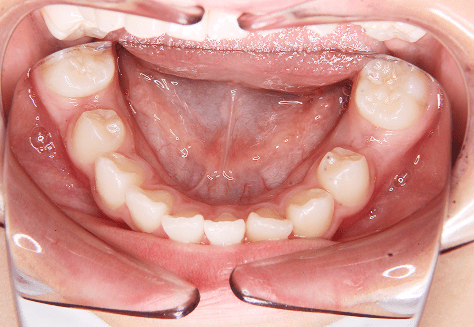

M.U

治療前

治療後

主訴

下の歯が特にガタガタなのが気になる。上の前歯が1本反対になっている。

診断

下顎前突・叢生・反対咬合

年齢/性別

20代/男性

抜歯部位

非抜歯

使用装置

上下インビザライン(PBM使用)

保定装置

ビベラリテーナー

診察料金

5,500円×16回

治療期間

1年7カ月